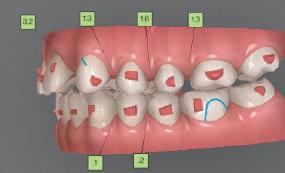

20 Dental Tribune Bulgarian Edition / октомври 2022 г. П ациентите със завършен растеж и скелетни проблеми обикновено представляват предизвикателство за ортодонт ската практика. Необходимостта от изваждане на зъби в комбинация с особеностите на възрастовата ортодонтия изисква особено внима ние. Фокусът върху критично важното значение на позицията на долните резци във връзка с дългосроч ната стабилност и постигането на оптимални оклузални взаимоотношения при затварянето на екстракционните пространства лесно може да излезе извън контрол. Когато към тези чисто кли нични проблеми се добави и стресът от натоваре ната практика, предизвикателството става още по-голямо. Всички тези фактори налагат използ ването на доказан подход с ясни и последовател ни стъпки, в което се разкрива силата на дисциплината „Алекзандър“ – предвидим протокол през целия процес на елиминиране на ротациите, ниве лиране на дъгите, затваряне на екстракционните пространства и финализиране на случая. Именно такъв е и случаят, който презентираме –екстракционен, скелетен клас 3 при възрастен па циент, лекуван по системата „Алекзандър“. ПРЕДВИДИМИ РЕЗУЛТАТИ ПРИ ПАЦИЕНТИ СЪС ЗАВЪРШЕН РАСТЕЖ И СКЕЛЕТЕН КЛАС 3, ИЗПОЛЗВАЙКИ ЕКСТРАКЦИОННО ЛЕЧЕНИЕ ПО ДИСЦИПЛИНАТА „АЛЕКЗАНДЪР“ Д-р Радой Димитров, България Преди започване на лечение клиничен случай | ортодонтия Фиг. 1а–1e Преди започване на лечение. Пациентът пристига в практиката с основното оплакване от невъзмож ност за нормално дъвчене. Снета е цялата необходима диагностична ин формация. Фиг. 1f–1h Снимки в профил и анфас. Фиг. 1i–1k Панорамна снимка, телерентгенография и анализ на телерент генография. Фиг. 1а Фиг. 1d Фиг. 1f Фиг. 1g Фиг. 1h Фиг. 1e Фиг. 1b Фиг. 1c Фиг. 1i Фиг. 1j Фиг. 1k

closed.

21Dental Tribune Bulgarian Edition / октомври 2022 г. ДИАГНОСТИЧНИ РЕЗУЛТАТИ: 1. Възраст на пациента: 21 години 2. Скелетен клас III (ANB 0) 3. Зъбен клас 3 4. Ръбцова захапка във фронта, кръстосана в дисталните участъци 5. Тясна горна челюст 6. Overjet – 0 мм, Overbite – 0 мм 7. Несъответствие на горната с долната средна линия 8. Единични контакти в ЦО 9. Хиподивергентен тип на растеж SN/MP – 33.5 10. Неравен гингивален контур 11. Неравна линия на усмивката 12. Тенденция за рецесии в долен фронт ПРЕПОРЪЧИТЕЛНО ЛЕЧЕНИЕ: Пълно ортодонтско лечение с метални брекети „Алекзандър“ Корекция на клас 3 захапката в областта на кучешките зъби с екстракция на първите пре молари в долна челюст Корекция на кръстосаната захапка в дистални участъци Коригиране на ръбцовата захапка във фронта Подобряване на ОJ и OB на пациента Стрипинг в долен фронт Подреждане на зъбите в горната и долната челюст Професионално хигиенизиране и профилактични дентални прегледи са препоръчителни на всеки 6 месеца. 1-ви месец След 1 месец са залепени брекети в горната челюст – поставена е еластична дъга. 016 NiTi. В долната челюст са елиминирани ротациите, поставена е стоманена дъга. 016SS, закалена с ток, и еластична верижка за затваряне на пространствата. 3-ти месец В долната челюст е поставена трета дъга – 17 x 25 NiTi с къси лигатури и верижка

В горната челюст се затварят пространствата с дъга .016SS и верижка. 5-и месец На 5-ия месец след залепяне на брекетите в долната челюст е поставена стоманена дъга 16 x 22 SS с четвъртито сечение, омега луп и тай бек. В горната челюст е поставена дъга 17 x 25 NiTi. Поради липсата на стабилни оклузални контакти са поставени лингвални верижки в областта на моларите, за да се предотврати нежелана ротация на 7-ите зъби. 6-и месец На 6-ия месец от началото на лечението са екстрахирани долните първи премолари, поставена е дъга 16 x 22 SS със затваряща чупка teardrop. Чупката се активира всеки месец по 1 мм с чинч-бек. клиничен случай | ортодонтия СТЪПКИ НА ЛЕЧЕНИЕТО Начало на лечението Лечението започва с поставяне на апарат за бърза експанзия в горната челюст. През първия месец от лечението са направени 24 оборота на апарата за експанзия. Залепени са брекети в долната челюст, поставена е дъга 17x25 CuNiTi, като са предпи сани клас 3 ластици (1/4”,4 1/2 oz) по време на сън, за да се осигури контрол върху торка на долните резци. Фиг. 2а Фиг. 3a Фиг. 4a Фиг. 3b Фиг. 4b Фиг. 3c Фиг. 4c Фиг. 3d Фиг. 4d Фиг. 3e Фиг. 4e Фиг. 5a Фиг. 5b Фиг. 5c Фиг. 5d Фиг. 5e Фиг. 6a Фиг. 6b Фиг. 6c Фиг. 6d Фиг. 6e Фиг. 7a Фиг. 7b Фиг. 7c Фиг. 7d Фиг. 7e Фиг. 2b Фиг. 2c Фиг. 2d

Dental Tribune Bulgarian Edition / октомври 2022 г.22 клиничен случай | ортодонтия 14-и месец В горната и долната челюст са поставени последни стоманени дъга с омега луп и тай бек – 17 x 25 SS с четвъртито сечение. Назначени е ластик за средната линия в комбинация с клас 3 ластик (1/4”, 6 1/2 oz). Контролни рентгенографии 13-и месец Екстракционните пространства са затворени. Направена е контролна панорамна снимка за оценка позицията на корените. Взето е решение за презалепване на брекетите на 12, 22 и пръстените на 36 и 46. 21-ви месец Средната линия в горната и долната челюст съвпадат. Ластиците са спрени. Свалени са пръстените и брекетите в горната и долната челюст, зигзаг ластици не са използвани поради благоприятните оклузални взаимоотношения. Фиг. 11j Ортопантомография в края на лечението. Фиг. 11k Телерентгенография след края на лечението. Фиг. 11l Анализ на телерентгенографията след лечението. Фиг. 11m Последователност на дъгите в горната и долната челюст Фиг. 11n Суперимпозиция на PreOp и PostOp ортопантомографии. 10-и месец Затварянето на пространствата е предвидимо и контролирано, без да се отварят пространства в зъбната дъга. Фиг. 8a Фиг. 8b Фиг. 8c Фиг. 8d Фиг. 8e Фиг. 10a Фиг. 10b Фиг. 10c Фиг. 10d Фиг. 10e Фиг. 9a Фиг. 9b Фиг. 9c Фиг. 9d Фиг. 9e Фиг. 9f Фиг. 11a Фиг. 11f Фиг. 11j Фиг. 11l Фиг. 11m Фиг. 11n Фиг. 11k Фиг. 11g Фиг. 11h Фиг. 11i Фиг. 11b Фиг. 11c Фиг. 11d Фиг. 11e

Dental Tribune Bulgarian Edition / октомври 2022 г. 23клиничен случай | ортодонтия реклама Лечението е продължило 21 месеца. Проведено е домашно избелване с индивидуални шини. За автора: Д-р Радой Димитров завършва с отличие Факултета по дентална медицина към МУ–София през 2015 г. В продължение на 5 години работи в няколко водещи практики в София, като през 2019 г. заедно със своята съпру га д-р Траяна Димитрова основават собствена практика в гр. Гоце Делчев –Dimitrovi Dental Care. Посещава редица курсове за повишаване на квалификаци ята, но най-сериозен тласък в развитието на ортодонтската си практика получава след завършването на комплексната ортодонтска програма, воде на от д-р Иван Горялов, базирана на дисциплината „Алекзандър“ – система с повече от 50 години опит в целия свят. Д-р Димитров е член на Българския изследователски клуб „Алекзандър“. Взе ма участие като гост-лектор в симпозиума с международно участие The Power of the Alexander Discipline, който се проведе на 14–15.05.2022 г. С д-р Ди митров можете да свържете на тел. +359885 252 025. Заключение Представеният случай е ярък пример за възможностите и красо тата на дисциплината „Алекзандър“ – приложен е утвърден под ход с ясни правила и са постигнати очакваните цели. Резулта тът ще бъде дългосрочно стабилен, тъй като са спазени всички правила, които се отнасят към максимално комфортната пози ция на зъбите в края на лечението. Постигнати са красива усмив ка и стабилна оклузия. ПОСТИГНАТИ РЕЗУЛТАТИ ОТ ЛЕЧЕНИЕТО 1. Коригирана ръбцова захапка 2. Коригирана клас 3 захапка в областта на ку чешките зъби 3. Коригирана кръстосана захапка в дисталните участъци 4. Коригиран овърджет и овърбайт 5. Разширена е горната зъбна дъга 6. Подредени зъби в горната и долната челюст 7. Постигната е стабилна захапка с множество контакти в ЦО 8. Драматично е подобрена дъвкателната функ ция 9. Подобрена е линията на усмивката ДРУГИ ПРОВЕДЕНИ ДЕНТАЛНИ ПРОЦЕДУРИ 1. Домашно избелване на зъбите 2. Екстракция на мъдреците Фиг. 12a Фиг. 12b Фиг. 12c Фиг. 12eФиг. 12d Фиг. 12f Фиг. 12g Информация за дати, цени и отстъпки www.bracescourses.com 0889 22 55 01 Практически курсове лектор д-р Иван Горялов Дисциплината „Алекзандър“ ПЪТЯТ КЪМ СУПЕРУСМИВКИТЕ 100% връщане на цялата сума, ако не сте удовлетворени след преминаване на Ниво 1 Директно и индиректно залепяне на брекети Анализ, диагноза и план на лечение Лечение на клас 2 дълбока захапка Екстракционно лечение Лечение на клас 3 отворена захапка НИВО 5НИВО 1 НИВО 2 НИВО 3 НИВО 4